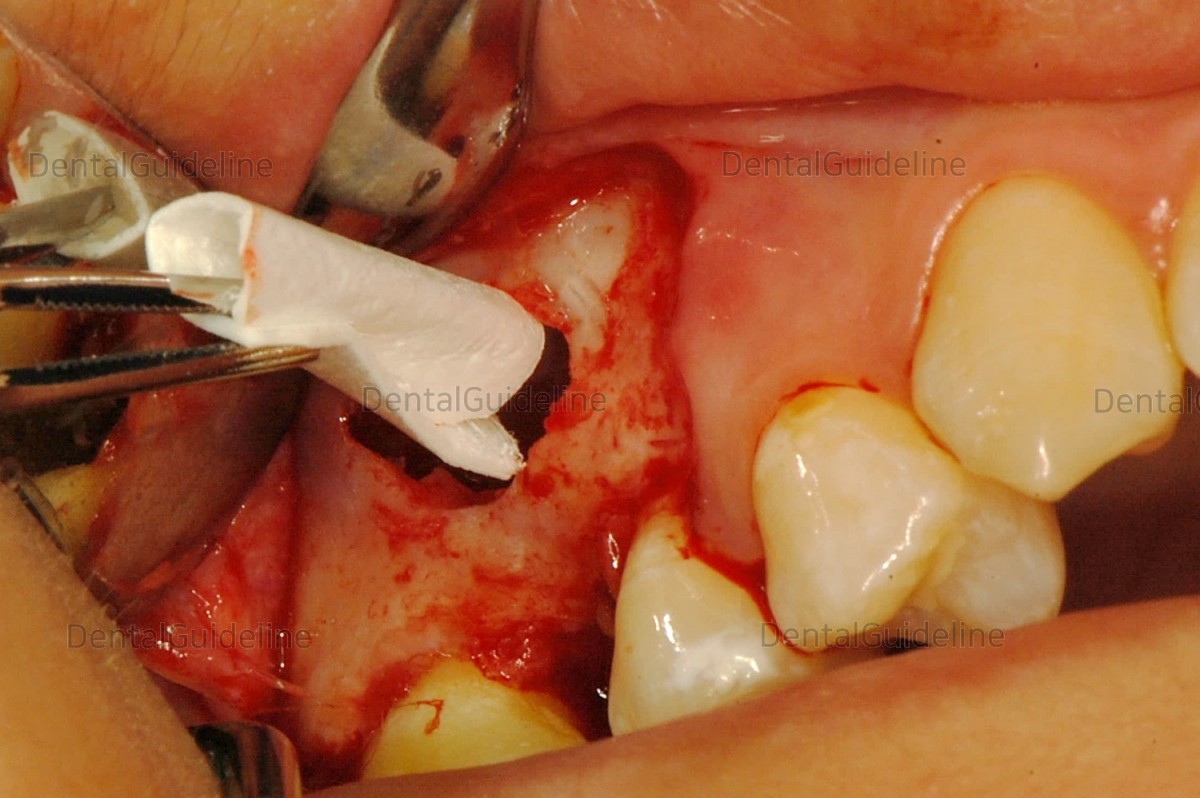

6. To protect the roof of the maxillary sinus membrane, an

absorbable collagen membrane is placed under the raised sinus membrane.

7. By placing the collagen membrane in this way, the problem

caused by the perforation of the maxillary sinus membrane that might not have

been noticed can also be solved.